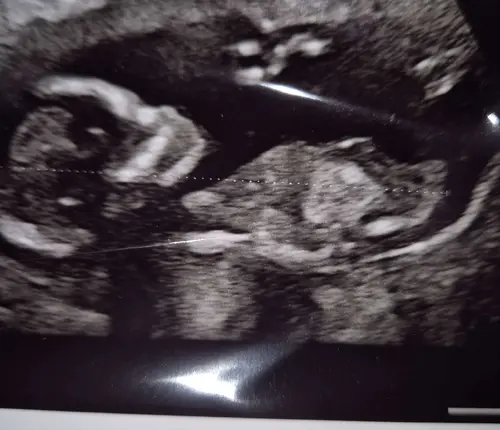

We hebben voor de NUB-theorie een groot topic openstaan: https://community.24baby.nl/forum/zwanger/het-grote-nub-topic-deel-54-j2paQmA?page=1. Om het forum overzichtelijk te houden, sluit ik daarom dit topic.